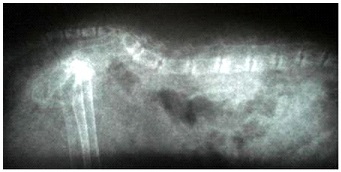

Sokkal gyakoribb, és gyakoribb a kölykök etetik hús és / vagy a belsőségek (máj, szív), valamint a kiegyensúlyozatlan, mint a kalcium és a foszfor étrend. Hús tartalmaz nagy mennyiségű foszfor és a kalcium nem elegendő. Annak ellenére tartozó kutyák és macskák húsevő, a diéta kell jelen lenni nemcsak a hús, hanem a csontok, amelyek a természetben kalcium szállítók testébe egy ragadozó. Így, szekunder mellékpajzsmirigy-túlműködés következménye a nem megfelelő kalcium-fogyasztás egy állat, ahol a mellékpajzsmirigy termel fölös mennyiségű PTH-t és a kalcium-kezd lemosható csontokból a vérbe, hogy fenntartsák az egyensúlyi foszfor. A röntgenfelvételek a hiperparatiroidizmus megfigyelhető diffúz csontvesztés, csökken az intenzitás a árnyékok. Gyakran a röntgenfelvételen kiderült subperiosteal csonttörések.

- Röntgen vizsgálat;